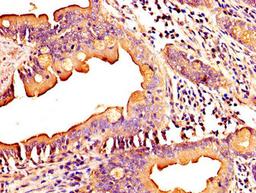

IHC image of CSB-PA873607LA01HU diluted at 1:300 and staining in paraffin-embedded human small intestine tissue performed on a Leica BondTM system. After dewaxing and hydration, antigen retrieval was mediated by high pressure in a citrate buffer (pH 6.0). Section was blocked with 10% normal goat serum 30min at RT. Then primary antibody (1% BSA) was incubated at 4°C overnight. The primary is detected by a biotinylated secondary antibody and visualized using an HRP conjugated SP system.